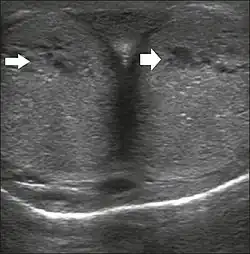

Penile ultrasonography with doppler can be used to examine the erect penis. Most cases of ED of organic causes are related to changes in blood flow in the corpora cavernosa, represented by occlusive artery disease (in which less blood is allowed to enter the penis), most often of atherosclerotic origin, or due to failure of the veno-occlusive mechanism (in which too much blood circulates back out of the penis). Before the Doppler sonogram, the penis should be examined in B mode, in order to identify possible tumors, fibrotic plaques, calcifications, or hematomas, and to evaluate the appearance of the cavernous arteries, which can be tortuous or atheromatous.[48]

Erection can be induced by injecting 10–20 μg of prostaglandin E1, with evaluations of the arterial flow every five minutes for 25–30 min (see image). The use of prostaglandin E1 is contraindicated in patients with predisposition to priapism (e.g., those with sickle cell anemia), anatomical deformity of the penis, or penile implants. Phentolamine (2 mg) is often added. Visual and tactile stimulation produces better results. Some authors recommend the use of sildenafil by mouth to replace the injectable drugs in cases of contraindications, although the efficacy of such medication is controversial.[48]

Before the injection of the chosen drug, the flow pattern is monophasic, with low systolic velocities and an absence of diastolic flow. After injection, systolic and diastolic peak velocities should increase, decreasing progressively with vein occlusion and becoming negative when the penis becomes rigid (see image below). The reference values vary across studies, ranging from > 25 cm/s to > 35 cm/s. Values above 35 cm/s indicate the absence of arterial disease, values below 25 cm/s indicate arterial insufficiency, and values of 25–35 cm/s are indeterminate because they are less specific (see image below). The data obtained should be correlated with the degree of erection observed. If the peak systolic velocities are normal, the final diastolic velocities should be evaluated, those above 5 cm/s being associated with venogenic ED.[48]